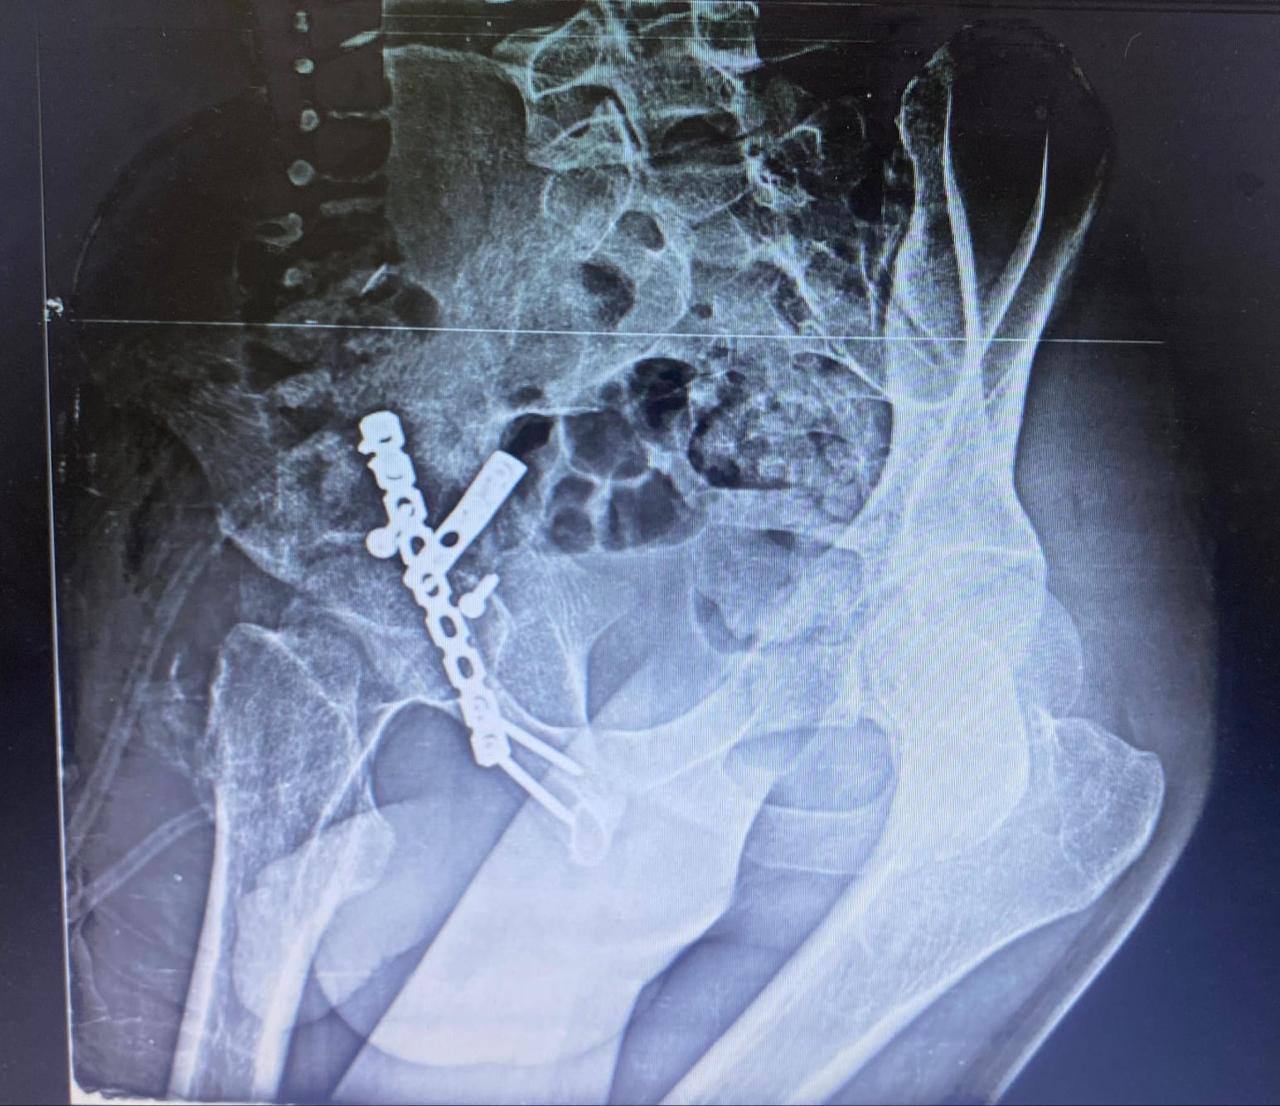

أ.د/ حسام الدين جاد – رئيس قسم جراحة العظام نجحت وحدة جراحات الحوض المتقدمة بقسم جراحة العظام والكسور في إجراء عملية معقدة لرد وتثبيت كسر مهمل بالجدار الخلفى للحق الحرقفى مع وجود خلع مهمل بالمفصل وتحرير العصب الوركى حيث انه حضر إلينا المريض يعانى من آلام فى الحوض وسقوط جزئى بالقدم بعد مرور شهرين من إصابته فى حادث وتم عمل اشعة فتبين وجود خلع مهمل مع كسر بالجدار الخلفى للحق الحرقفى بمفصل الفخذ وتم دخول الحالة للعمليات حيث تم استكشاف وتحرير العصب الوركى وعمل رد مفتوح للخلع وازالة التعظم بالانسجة المحيطة واعادة بناء الجدار الخلفى للحق باستخدام رقعة عظمية من داخل عظام الحوض وتثبيت الكسر بواسطة شرائح ومسامير وتم خروج المريض من العمليات بنجاح.